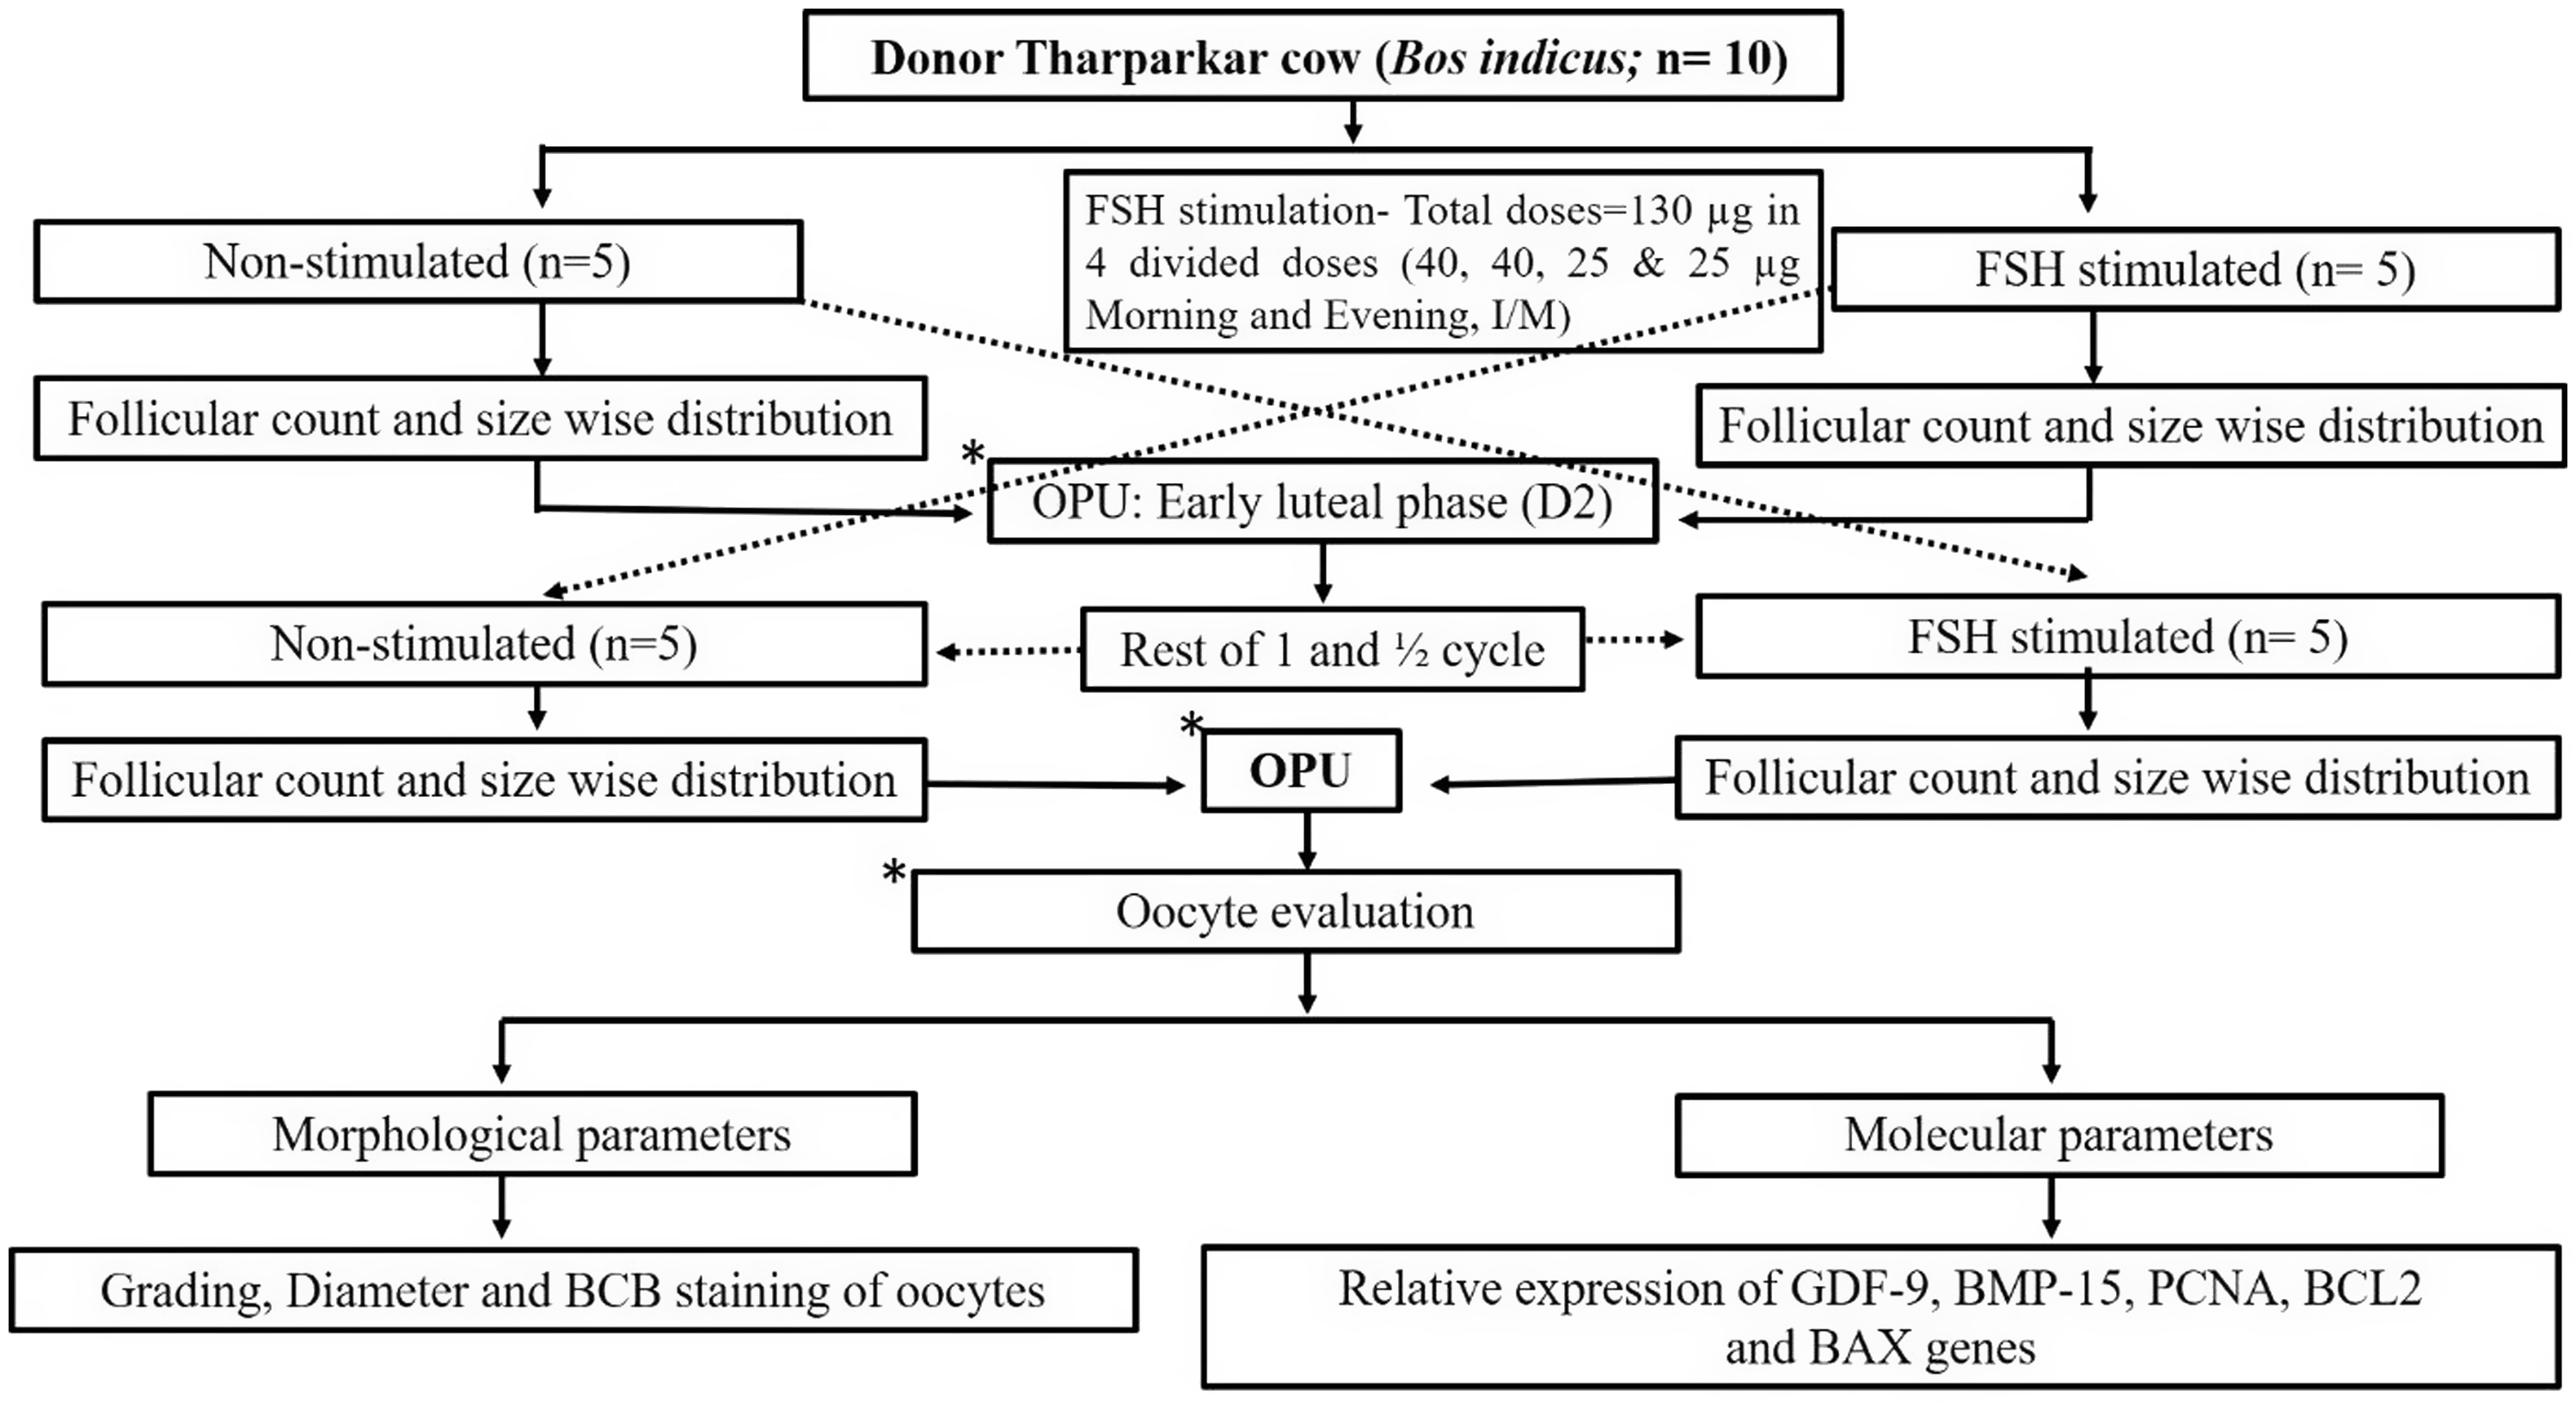

A lubricated transvaginal probe was inserted into the anterior vagina and positioned against the ovary for viewing and aspirating follicles. Data on follicle number and diameter were recorded using a caliper on a monitor image and categorized into groups i.e. follicles ≥6 mm and <6 mm. Once the ovary and target follicle were stabilized, follicular aspiration was performed by a single trained technician using a real-time B-mode ultrasound scanner (Draminski 4 Vet-slim, Poland) equipped with a multi-frequency (2–14 MHz) micro convex probe. During the entire OPU session, the needle and aspiration line were thoroughly rinsed with pre-warmed (37 °C) OPU recovery medium (IVF Bioscience, UK) to prevent blood clotting or oocytes from sticking to the tubing and collecting conical tube (50 ml). A negative pressure of 85 to 90 mm Hg was generated using a vacuum aspiration (Wireless) pump with a thermostat (WTA, Brazil) to create a vacuum and generate a fluid flow of 15–20 ml per min. for both groups. Transvaginal ultrasonographic images of an FSH-stimulated and non-stimulated donors ovaries before (Figure 2 A & 2 C) and after Ovum Pick up (Figure 2 B & 2 D) respectively. Oocyte recovery rate (%) was calculated by using the following formula:

Figure 2. Transvaginal ultrasonographic images of stimulated and non-stimulated ovaries. (A) Partially stimulated ovary prior to OPU showing numerous follicles of ≥ 6mm. (B) Partially stimulated ovary after transvaginal oocytes aspiration showing very few left over small size follicles. (C) Non-stimulated ovary on day −2 of oestrous cycle prior to OPU showing numerous growing follicles of < 6mm. (D) Non-stimulated ovary on day −2 of oestrous cycle after transvaginal oocytes aspiration showing very few left over follicles.